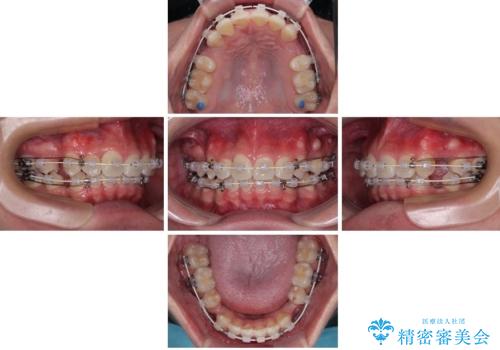

- 矯正装置

- 審美装置

矯正装置には白いプラスチックブラケットと白いコーティングワイヤーを使用し、見た目にも配慮した治療を行いました。

治療後には、デコボコと正中の位置が改善し、見た目だけでなく歯磨きがしやすい清潔なお口の環境を手に入れました。